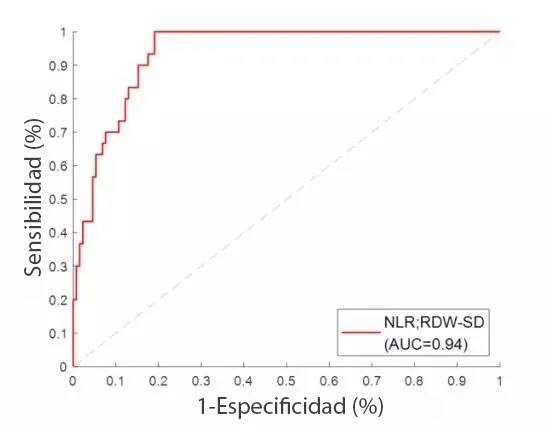

En vista de las claras diferencias de RDW-SD entre los casos moderados y graves, se establece una regresiÃġn lineal de NLR y RDW-SD, con un AUC a 0,94. Cuando el valor de corte es 1,06, la sensibilidad a la hora de distinguir casos moderados de los graves es del 90 %, y la especificidad del 84,7 %.?De modo que, cuando el resultado del NLR y RDW-SD es superior a 1,06, serÃḂ altamente recomendable seguir de cerca al paciente en caso de que siga empeorando y sea necesario un traslado a la UCI.?Este resultado puede ofrecer informaciÃġn valiosa para facilitar y acelerar una decisiÃġn clÃnica mÃḂs exacta que resulte en mejores desenlaces clÃnicos para los pacientes.

CentrÃḂndose en los resultados del NLR y RDW-SD, se introdujeron una regresiÃġn lineal y un anÃḂlisis de la curva ROC con el fin de establecer el parÃḂmetro NLR y RDW-SD como indicador para identificar casos graves. Con un AUC que alcanza el 0,94, este parÃḂmetro puede proporcionar informaciÃġn Ãẃtil para ayudar a los médicos a decidir en qué categorÃa se deberÃa asignar al paciente y qué tratamiento deberÃa recibir. No obstante, es importante puntualizar que este es un estudio retrospectivo y que se ha de validar su aplicabilidad con mÃḂs casos clÃnicos.